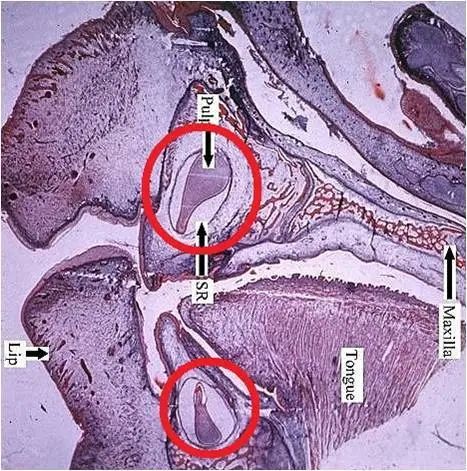

人们都知道,要想生娃,得先怀胎。同理,要有牙,也得先有牙齿的胚胎——牙胚。人的胚胎是在母亲的子宫里发育,而牙胚则是在颌骨里发育。

失踪的牙齿其实是“未曾有过”,因为颌骨里根本没有牙胚。没有牙胚,又如何长得出牙齿呢?这个答案是不是既在意料之外,又在情理之中呢?